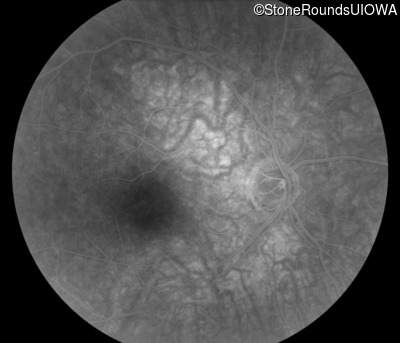

Fluorescein Angiography - Right - 20/20 -1

Exemplar